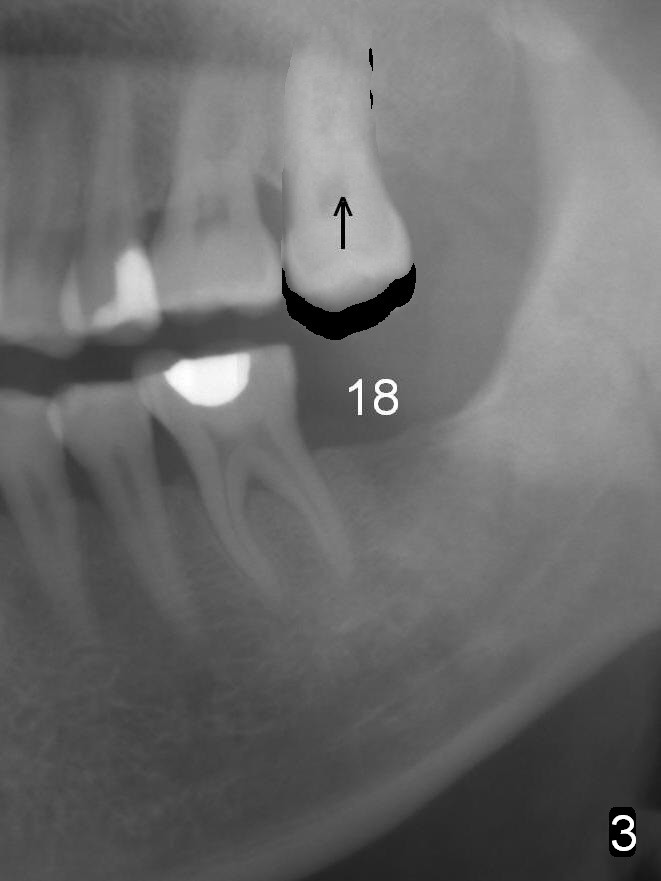

In fact, the tooth 15 had basically no extrusion 6 years earlier (Fig.2) with even occlusal plane. When the tooth is intruded orthodontically, the occlusal plane may be not even (Fig.3). When the implant at #18 osteointegrates (Fig.4 green), fabricate a provisional (grey rectangle) with higher mesial occlusal surface. For certain period of time, the tooth #15 may change its axis so that the mesial portion of the tooth may be intruded more (Fig.5 arrow).

Four months post intrusion, the tooth #15 is distalized instead (Fig.9 arrow). To facilitate mesialization, the power chain is engaged into the mesiobuccal slot (Fig.10 <). It is 1 month after the change in position of the power chain. Has the tooth mesialized? Regional orthodontic devices are placed, but the patient is not cooperative, refusing any intrusion treatment. Prosthetic intrusion will be tried once the implant at #18 osteointegrates.